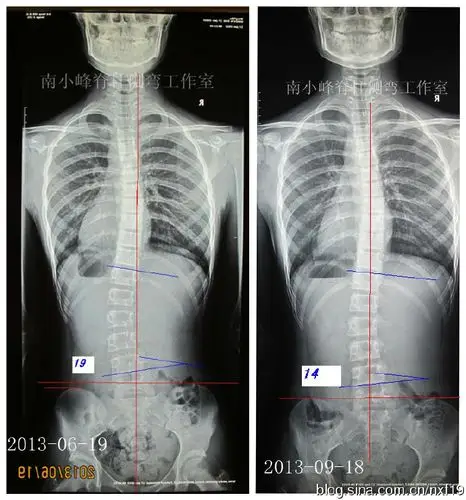

轻度脊柱侧弯要不要穿支具矫形